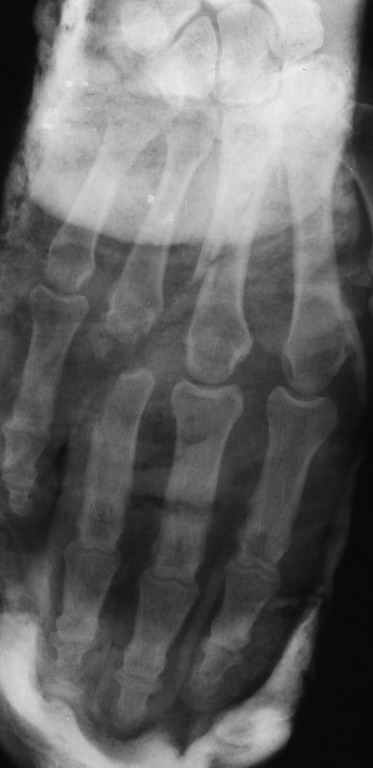

Диагноз: Стойкая Смешанная дермотеногенная контрактура 3,4 пальца правой кисти.